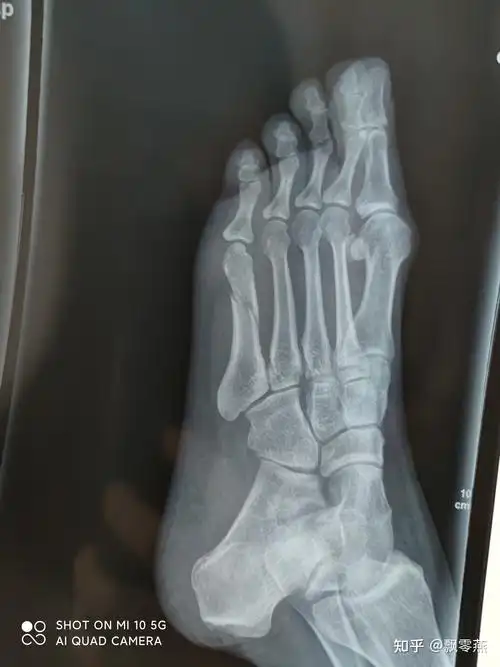

10月15日手术.已经术后20天 请问什么时候可以走路,片子是术后3天

脚撕脱骨折,没固定,一个多月了还是肿痛,分别拍了片子,现在的片子愈合

外科医生帮我看看脚的片子

医生求解答.这是我脚崴了,受伤七天后照的,严重不?

看个足部的片子